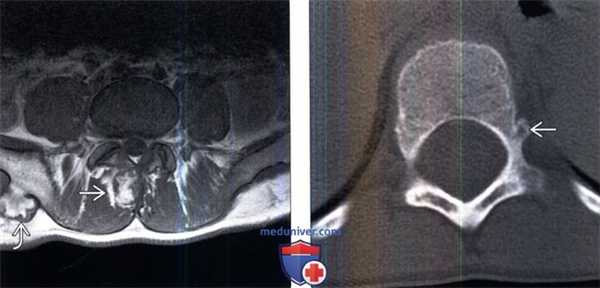

(Слева) Аксиальный срез, Т1-ВИ: крупная остеохондрома, исходящая из остистого отростка L4, центральное костномозговое пространство характеризуется гиперинтенсивностью сигнала, периферический хрящевой колпачок гипоинтенсивен. В области правого подвздошного гребня видна остеохондрома более классического вида «цветной капусты».

(Справа) Аксиальный КТ- срез, пациент с ВМЭ: визуализируется небольшой костный вырост в области левого корня дуги позвонка с признаками кортико-медуллярной непрерывности с подлежащей костью.